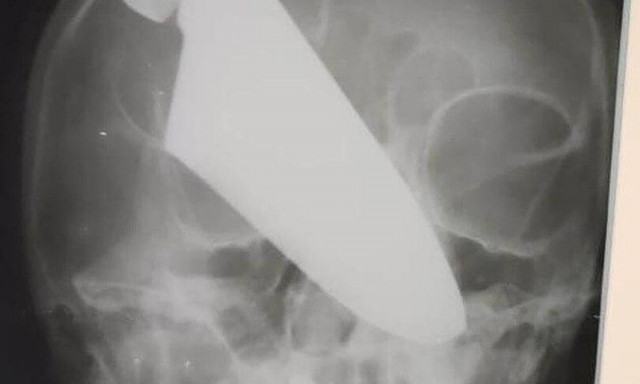

Μπροστά σε ένα απίστευτο περιστατικό βρέθηκαν γιατροί σε νοσοκομείο του Κράσνονταρ της Ρωσίας, όταν μια γυναίκα βρέθηκε στα επείγοντα με ένα μαχαίρι καρφωμένο στη μύτη της!

Η γυναίκα, το όνομα της οποίας δεν δόθηκε στη δημοσιότητα, είχε στη μύτη της ένα μαχαίρι 25 εκατοστών μετά από επίθεση που δέχτηκε στο δρόμο από ληστή, ο οποίος συνελήφθη λίγο αργότερα.

Μετά από μια επέμβαση που κράτησε πάνω από τέσσερις ώρες, το μαχαίρι αφαιρέθηκε και δεν άφησε κάποιο πρόβλημα στην 60χρονη.